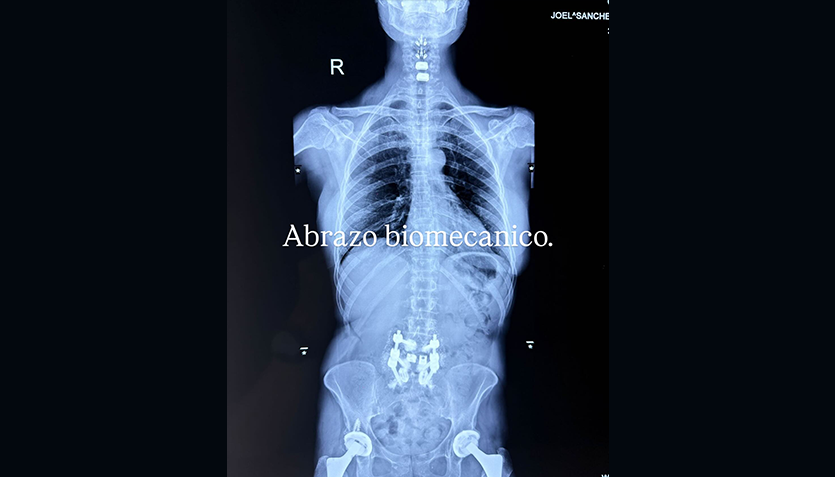

Alejandra Guzmán volvió a sorprender a sus seguidores al compartir en redes sociales una imagen de su columna tras su más reciente cirugía. La cantante fue hospitalizada de emergencia a inicios de octubre para una intervención en la zona lumbar, luego de años de complicaciones médicas derivadas de los biopolímeros que le inyectaron en 2009. En la radiografía se aprecian varios tornillos y prótesis que forman parte de su proceso de recuperación.

La imagen, acompañada por la frase “abrazo biomecánico”, se viralizó rápidamente, generando cientos de mensajes de apoyo de sus fanáticos. ‘La Guzmán’ ha demostrado una vez más su fortaleza frente a los desafíos médicos que ha enfrentado, confirmando que su historia de lucha y resiliencia continúa inspirando a miles de personas.